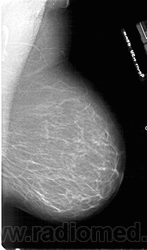

Жирная (не плотная) грудь

Умеренно плотная грудь

Плотная грудь

Маммограммы представляют собой изображения структур, проецируемых на плоскость: плотная грудная маммограмма, следовательно, состоит из многих других структур, которые необходимо проанализировать, чем более жирная, пустая грудь. По этой причине диагностировать рак молочной железы труднее для моложе, чем для пожилых женщин.

Нажмите на миниатюрные картинки, чтобы получить увеличенный размер.